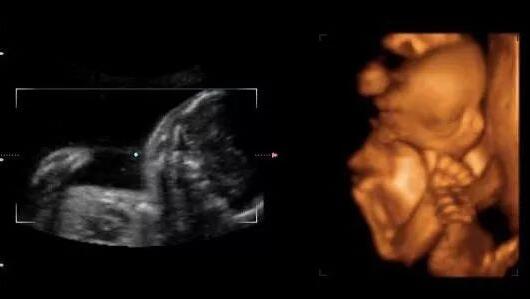

有一种说法,看B超单就能知道孩子的性别了。

男孩B超图片

一般来说,B超单上的数据有很多,比如双顶径、腹围、股骨长、胎囊、胎心次数等,还可以从B超中观察到胎盘、羊水、脐带、胎儿脊椎等情况。老一辈有些人的说法认为看怀孕40-50天时的B超单,观察孕囊的大小和形状就能看出胎儿的性别,孕囊形状是椭圆或圆形的是女宝宝,长条形的是男宝宝。

当然还有厉害的看单子上面双顶径和股骨长,头大腿短的是男孩,即双顶径-股骨长>2,头和腿相差小的是女孩。